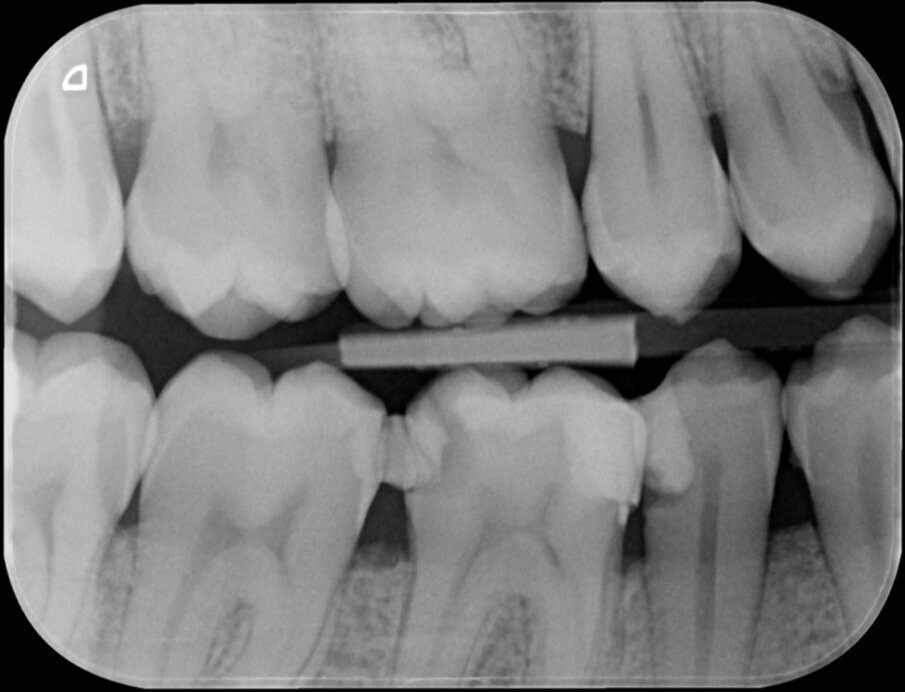

Vier jaar geleden meldde zich een patiënt in onze praktijk met heftige pijn in de regio 46. Na een blik op de bitewing en op de apicale röntgenopname (afbeelding 1 en 2) is de indicatie endodontische behandeling 46 snel gesteld.

De lengte van de kanalen was ongeveer 25 millimeter. Na openen en toegang verkregen te hebben tot het bovenste 2/3 gedeelte van de radix werd het apicale deel van de kanalen benaderd met behulp van SS K-vijlen 08 en 10. We maakten de kanalen doorgankelijk (‘patent’, een term van professor Herbert Schilder) en maakten het kanaal zodanig glad dat we een nieuwe rechte K-vijl zonder te manoeuvreren moeiteloos op de door de elektronische lengtemeter vastgestelde lengte kunnen laten glijden.

Wat mij vooral opviel was de teleurstellende restauratieve begin situatie (46m+d en 45d).

Zeker in een verdere gave dentitie!

Heftige pijn in deze regio is zeker verklaarbaar.

Maar was er al sprake van een irreversibel proces?

Was goed restauratief ingrijpen op zowel 46 als 45 misschien al voldoende geweest?